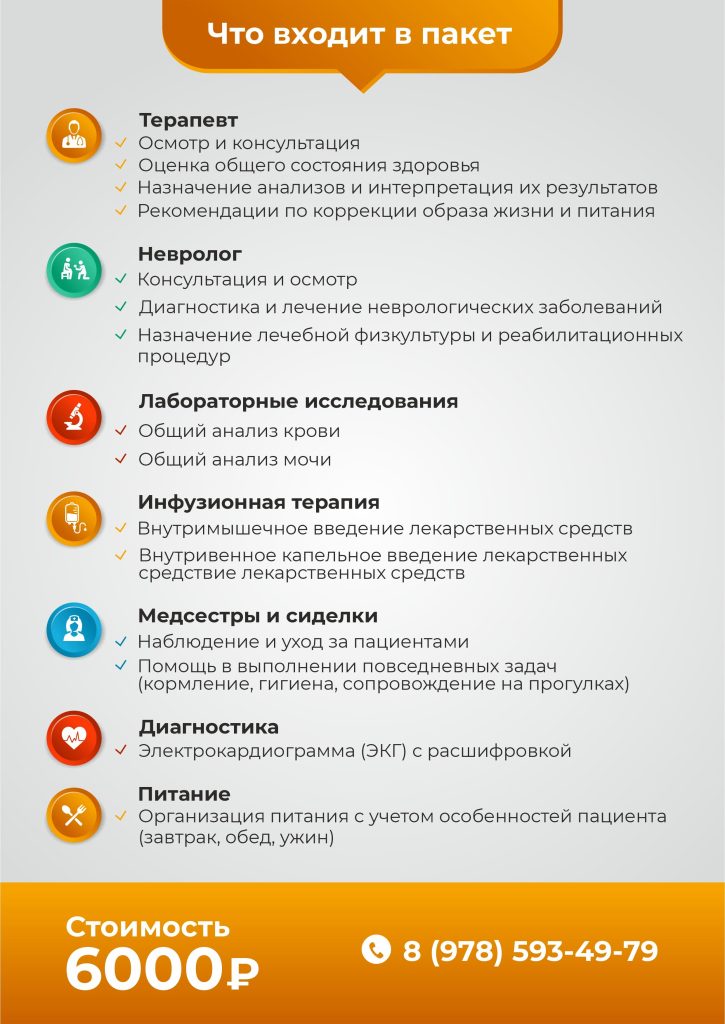

| Услуга | Стоимость |

|---|---|

| Прием врача первичный | от 2000 ₽ |

| Прием врача повторный | от 1800 ₽ |

| Прием кандидата медицинских наук первичный | от 4500 ₽ |

| Прием кандидата медицинских наук повторный | от 4000 ₽ |

| Диагностика заболевания | от 2500 ₽ |

| Взятие анализов (крови, мочи, кала и так далее) | от 1200 ₽ |

| Комплексное лечение в стационаре (цена за сутки) | от 4500 ₽ |

| Консилиум (гл.врач, психиатр, психиатр-нарколог, невролог, терапевт, психотерапевт, психолог) | от 15000 ₽ |

| Перевозка больного | от 1500 ₽ |

| Выезд врач на дом | от 8000 ₽ |